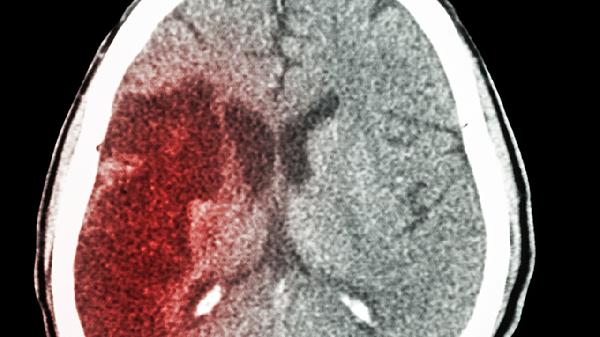

外伤脑出血后遗症主要有运动功能障碍、语言障碍、认知功能下降、情绪行为异常、癫痫发作等。外伤脑出血是指头部受到外力作用导致脑组织血管破裂出血,可能由交通事故、高处坠落、暴力打击等因素引起,严重程度与出血量、部位及救治时机密切相关。

外伤脑出血后遗症的康复需要多学科协作,除规范用药外,建议保持低盐低脂饮食以控制血压,每日进行30分钟有氧训练促进神经功能重塑。家属应协助患者建立规律作息,定期复查头颅CT评估恢复情况。若出现头痛加剧或意识改变需立即就医。